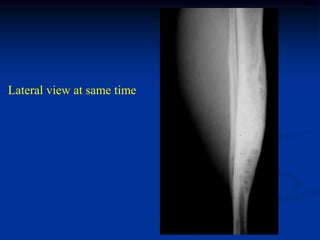

3.5 years later showing

good healing and no

progression of disease

Lateral view at same time